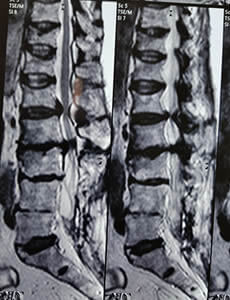

Hernia de Disto

¿Tienes una hernia de disco? ¿Dolor de Ciática? ¿Dolor de Espalda?